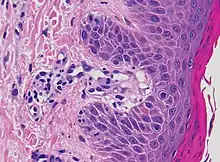

| Lichen planus | Irregular epidermal hyperplasia with a jagged “sawtooth” appearance, compact hyperkeratosis or orthokeratosis, foci of wedge-shaped hypergranulosis, basilar vacuolar degeneration, slight spongiosis in the spinous layer, and squamatization. The dermal papillae between the elongated rete ridges are frequently dome shaped. Necrotic keratinocytes can be observed in the basal layer of the epidermis and at the dermal-epidermal junction. Eosinophilic remnants of anucleate apoptotic basal cells may also be found in the dermis and are referred to as “colloid or civatte bodies”. Whickham striae are usually seen in the areas of hypergranulosis. Vacuolar degeneration at the basal layer may be noted leading to focal subepidermal clefts (Max Joseph spaces). Squamatization occurs as a result of maturation and flattening of cells in the basal layer. It happens in areas of marked hypergranulosis with prominence of the sawtooth pattern of rete ridges. Wedge-shaped hypergranulosis can occur in the eccrine ducts (acrosyringia) or hair follicles (acrotrichia). In the hypertrophic subtype, the associated hyperkeratosis, parakeratosis, hypergranulosis, papillomatosis, acanthosis, and hyperplasia markedly increased with thicker collagen bundles forming in the dermis. Moreover, the rete ridges are more elongated and rounded as opposed to the typical sawtooth pattern. In atrophic LP, loss of the rete ridges and dermal fibrosis is prominent. In vesiculobullous LP, the disease progression is quicker. Hence, some of the distinctive features such as hyperkeratosis, hypergranulosis, or dense lymphocytic dermal-epidermal infiltrate may not be present. LP lesion may resolve with residual hyperpigmentation caused by a persistent increase in the number of melanophages in the papillary dermis.[9] | ![]() | ![]() |